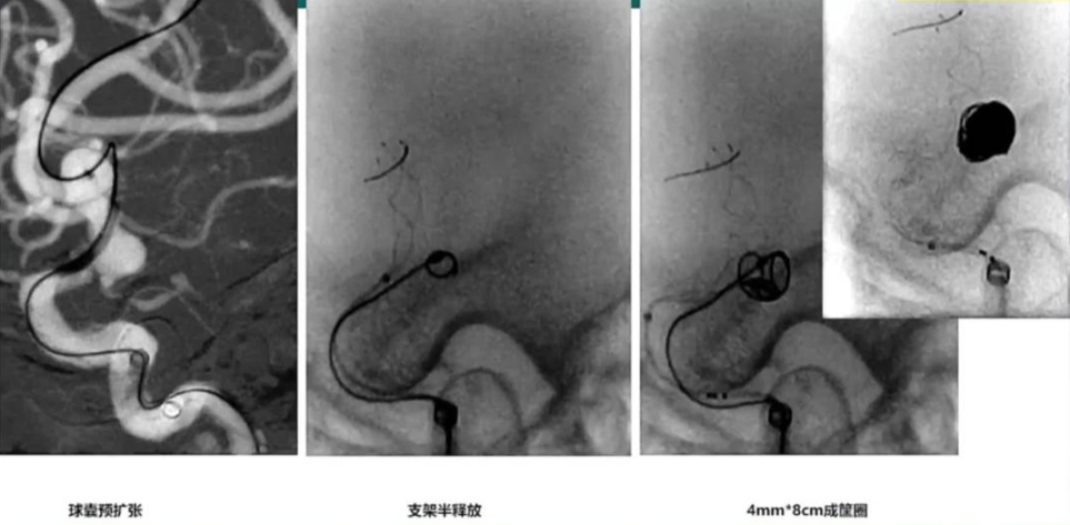

1.载瘤动脉近端重度狭窄,动脉瘤合并子囊,绝对宽径,

同侧A1发育不良,球囊预扩张,保障同侧血流;

2.动脉瘤绝对宽径,需要支架辅助,同时能适应近端狭窄,可选择编织支架,后扩张安全

3.支架大小和长度选择合适

4.成筐圈选择合理

5.后扩张球囊选择

Gateway球囊 2.0mm*15mm (预扩张)

支架 3.5mm*20mm

弹簧圈:

Scepter-C球囊 (后扩张)